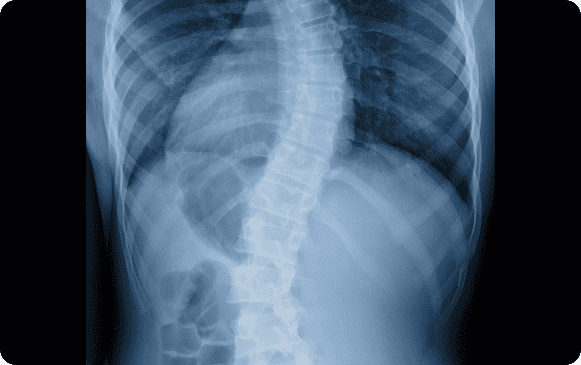

Scoliosis: A sideways curvature of the spine that can result from congenital factors, neuromuscular conditions, or osteoporosis. Treatment varies based on age, severity, and type, ranging from observation to braces or surgery in severe cases.